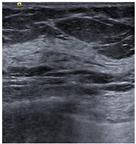

| Negative | Image | ![]() | ![]() | ![]() | ![]() |

| Number | 98 | 112 | 345 | 289 | |

| Positive | Image | ![]() | ![]() | ![]() | ![]() |

| Number | 47 | 49 | 161 | 184 | |